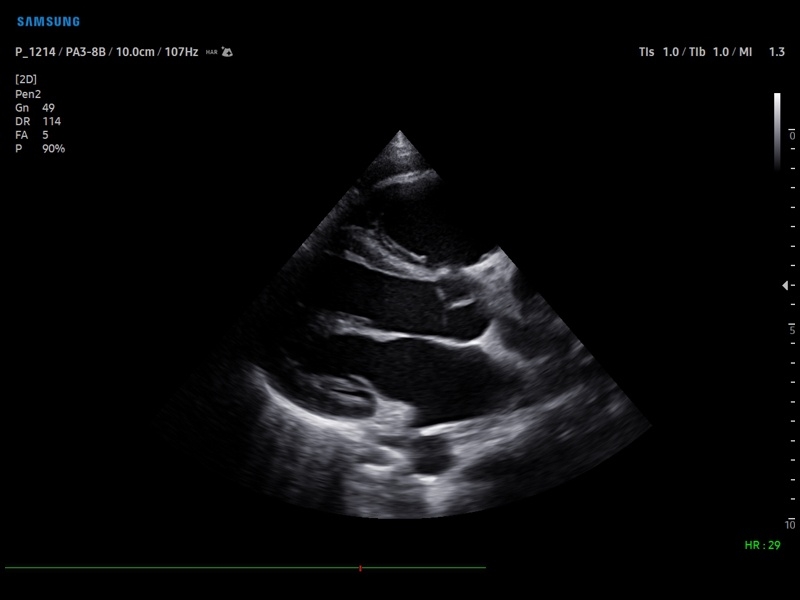

Ультразвуковой сканер V8-RUS является экспертным классом (премиальный уровень) и производится компанией Samsung Medison. Сканер V8 обеспечивает превосходное качество изображения благодаря использованию технологии Crystal Architecture™, которая включает в себя передовое аппаратное обеспечение, монокристальную технологию изготовления датчиков и сложную программную обработку ультразвуковых лучей.

Samsung Medison V8 представляет собой современную ультразвуковую систему, в которой воплощен многолетний опыт компании Samsung в создании эргономичного и интеллектуального диагностического оборудования. Система оснащена передовыми инструментами автоматизации, которые значительно упрощают рабочий процесс и повышают эффективность исследований.

• Кардиология

Кардиология:

• M - одномерный режим для исследования сердца, анатомический М-режим (необходим кардиопакет), CM - цветной М-режим (необходим кардиопакет).

• Кардиопакет: тканевый допплер (TDI) + анатомический М-режим + цветной М-режим (CM) + программное обеспечение.

• Пакет кардиологических исследований.

М-режим:измерение диаметра аорты, передне-заднего размера ЛП, толщины МЖП (систолическая и диастолическая), толщины ЗСЛЖ (систолическая и диастолическая), размеров ЛЖ и ПЖ (систолический и диастолический), ФВ (Teichholz).

B-режим:измерение диаметра аорты (восходящей, дуги, нисходящей, на уровне синусов Вальсальвы, на уровне створок аортального клапана), определение размеров ЛП и ПП (максимальный, минимальный, систолический, диастолический, переднее-задний, верхнее-нижний, медиально-латеральный), расчет объемов ЛП и ПП, объемов ЛЖ (метод "Площадь-Длина", метод дисков (Simpson)), массы миокарда ЛЖ, индекса массы миокарда ЛЖ.

CD-режим (ЦДК):измерение радиуса ПФСМР (PISA), полуколичественная оценка трансмитрального, транстрикуспидального, трансаортального и транспульмонального кровотока (оценка регургитации), оценка аномальных сбросов крови через МПП И МЖП.

PW-режим (импульсно-волновой допплер):автоматическая, полуавтоматическая и ручная трассировка допплеровского спектра митрального, аортального и трикуспидального клапанов, клапана легочной артерии, кровотока в выходном тракте ЛЖ и ПЖ (пиковая/средняя скорость, пиковый/средний градиент давления, время изоволюметрического расслабления ЛЖ, время ускорения, замедления, выброса), оценка кровотока легочных и печеночных вен.

CW-режим (постоянно-волновой допплер):программы расчета работы митрального, аортального и трикуспидального клапанов, клапана легочной артерии.

TD-режим (тканевой допплер):количественная оценка локальной сократительной функции стенок ЛЖ и ПЖ.